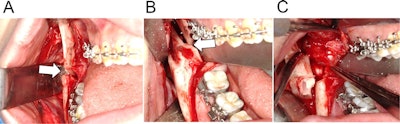

First, supersonic wave instruments were used to remove the split osteotomy stump of the distal segment of the right side of the jaw. This provided a better view of the distal inferior alveolar nerve, which had been ripped from the lower jaw foramen, they wrote.

Next, clinicians sutured the nerve stump and removed the right distal part of the buccal cortical bone to get a better view of the proximal side of the nerve. Because moving the fixed jaw could cause the nerve reconnection to fail, they repaired the nerve before performing the intermaxillary fixation. They stitched up the epineurium every 120° using three polyglycolic acid sutures while using a magnifying glass. They protected the repaired portion with absorbable polyglycolic acid mesh sheet.

Finally, clinicians put back the removed distal cortical bone. A monocortical titanium plate with five screws was used to fix the right side, and a plate with four screws was used to fix the left side. Surgeons checked her mouth opening and occlusion after they removed the wires between her upper and lower jaws and then closed the wound. X-rays taken after the procedures showed no abnormalities.